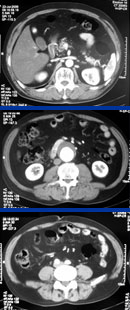

症例2

67歳 男性

検診異常

【起始・経過】

平成18年5月検診にて胸部大動脈瘤を指摘。

7月当院紹介受診。

【既往歴】

65歳 胃癌 → EMR

高血圧(+) 糖尿病(−) 喫煙歴(−)

【治療計画】

Gore社TAG stent留置術

胸部CT検査

腹部CTA検査